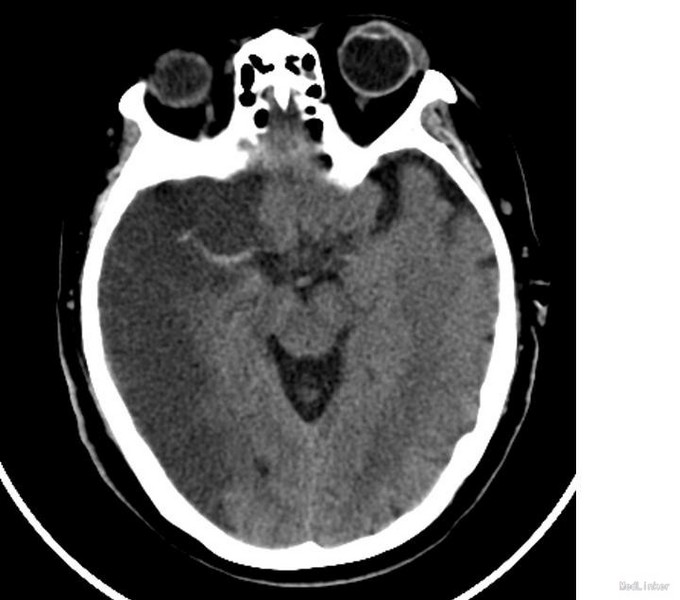

神清,语笨,双侧瞳孔等大正圆,D=3.0mm,光反应灵敏,双眼球各方向运动充分,无眼震,双侧鼻唇沟对称,伸舌右偏,右侧肌力Ⅴ级,肌张力正常,左侧肢体肌力0级,深浅感觉正常,共济运动正常,BCR L++ R++,PSR L++ R++,Babinski sign L-R-,Kernig征(-)颈软。 我院急诊头CT示:右侧半球新发梗塞,右侧大脑中动脉高密度影

急性脑梗塞临床常见,颅脑CT为首选检查,早期大面积梗塞表现:脑实质低密度征、大脑中动脉高密度征、局部脑肿胀。